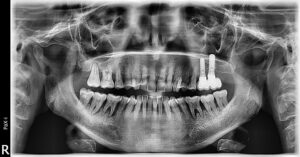

Knochenrückgang: nur durch Röntgen sicher zu erkennen

Die Sondierung zeigt, wie tief die Taschen sind. Aber sie zeigt nicht, wie viel Knochen bereits verloren gegangen ist. Dafür braucht es ein Röntgenbild.

Das OPG (Orthopantomogramm) ist eine Übersichtsaufnahme beider Kiefer. Es zeigt auf einen Blick, wo Knochen fehlt – und wie viel. Der Zahnarzt kann erkennen, ob der Abbau horizontal verläuft (gleichmäßig um den Zahn herum) oder vertikal (trichterförmig an einzelnen Stellen). Vertikale Defekte sind oft besser behandelbar.

Bei unklaren Befunden kommen zusätzlich Einzelaufnahmen (Zahnfilme) zum Einsatz. Sie zeigen einzelne Zähne detaillierter. Ein DVT (digitale Volumentomografie) kann in Ausnahmefällen hilfreich sein, etwa vor chirurgischen Eingriffen.

Ohne Röntgenbild keine vollständige Parodontitisdiagnose. Die Taschentiefe allein sagt nicht, wie viel Knochen noch vorhanden ist – und damit wie die Prognose aussieht.